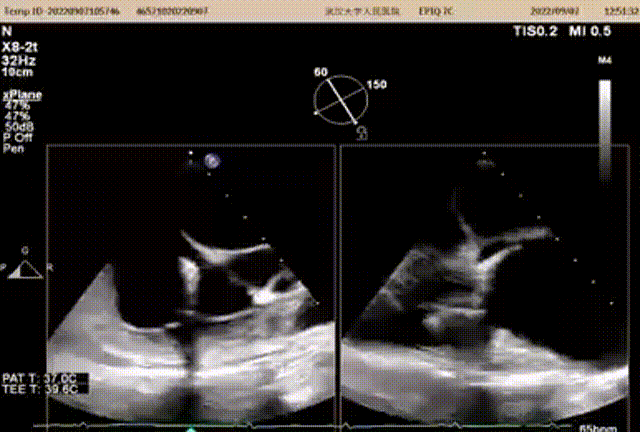

图1:术前TEE

术前TEE提示三尖瓣瓣叶活动可,无明显脱垂,隔瓣较短,反流束来源于前瓣及隔瓣交界处,前瓣及隔瓣对合缘保留良好,反流束同时向后隔交界延伸。